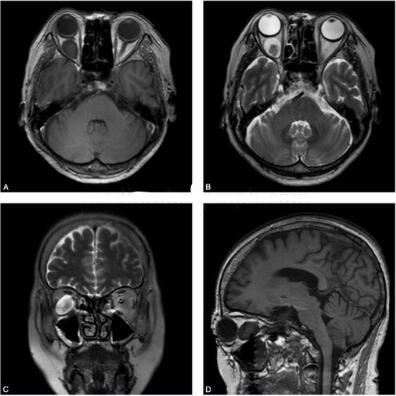

女性患者,62岁。2年前无明显诱因自觉双眼痛、头痛,无畏光流泪,无恶心呕吐,无视物不清。查体可见右侧眼球突出(图1、图2)。

图2 双眶MRI平扫:图A、图B为横断面T1WI、T2WI,图C、图D分别为冠状面T2WI和矢状面T1WI。右眶内球后结节呈等T1信号,T2WI示病变信号欠均匀,中心呈T2稍高信号,周围长T2高信号影,病变界限清楚,周围脂肪间隙清晰,与视神经关系密切,位于视神经外下方,局部可见视神经弧形移位